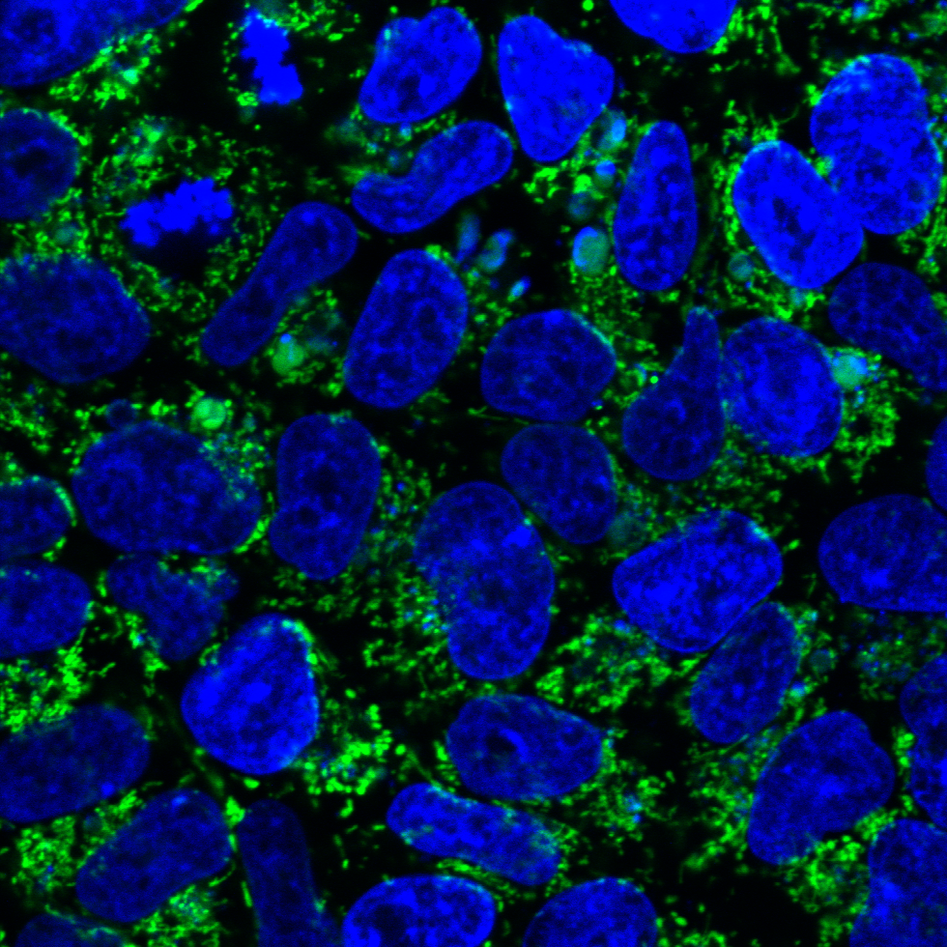

We are using stem-cells transformed from the patient’s own fibroblasts to study the mitochondrial disease caused by POLG mutations. These “induced pluripotent stem cells” (iPSC) offer a unique opportunity to model human disease in a renewable and tissue-specific manner. Thus far we have successfully generated neurones and all glial cell types, cardiomyocytes, and hepatocytes from these iPSCs.

We have established the required competence and facilities for human induced pluripotent stem cell (hiPSC) reprogramming and differentiation, enabling investigation of neuronal cells from patients and healthy controls. Validated iPSCs are differentiated to neural stem cells (NSCs) and regionalized neuronal subtypes, as well as astrocytes/ glial populations. A postdoctoral fellow in our group, Yu Hong, has developed brain organoids and will be using these both to investigate disease mechanisms and to test treatments.

- 2D: neural stem cells, DA neurons, motor neurons, generic neurons, astrocytes, oligodendrocytes and cardiomyocytes.